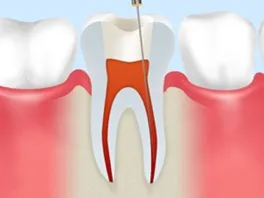

01 Step 1

感染した神経や組織を根管内から取り除きます。

02 Step 2

専用の測定器を用いて根管の長さを測定します。

03 Step 3

薬液で根管内部を繰り返し洗浄し、細菌を除去します。

04 Step 4

清掃後の根管に薬剤を充填し、再感染を防ぐよう密閉します。

05 Step 5

土台を築造し、被せ物を装着して機能回復を図ります。